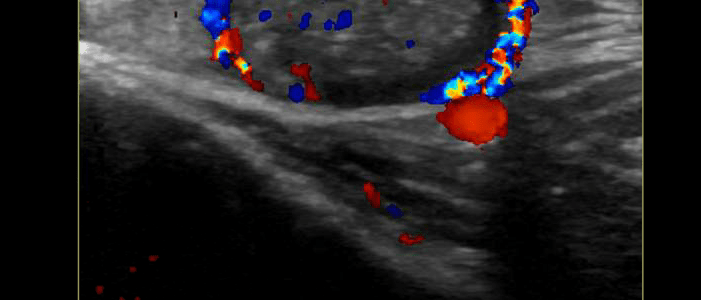

Intestinal Malrotation (Mid Gut Volvulus)

Intestinal malrotation due to the cessation of normal intestinal rotation in the fetus. The gastrointestinal tract divides into the foregut, midgut, and hindgut. The small and large intestines undergo rapid growth during weeks four and five of development. [1] It is theorized that the intestines outgrow the space in the abdominal cavity causing them to… Read More Intestinal Malrotation (Mid Gut Volvulus)